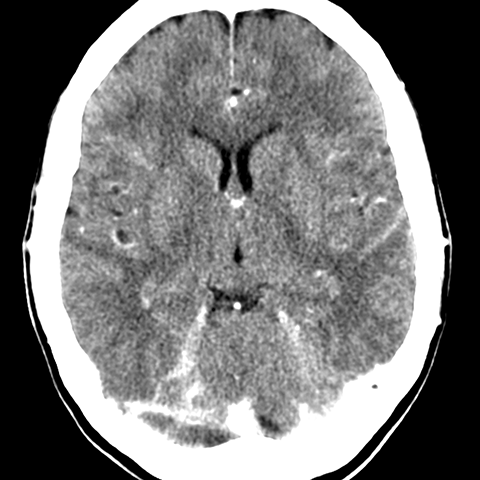

Basal Ganglia and Thalamus, CT [2 of 6]